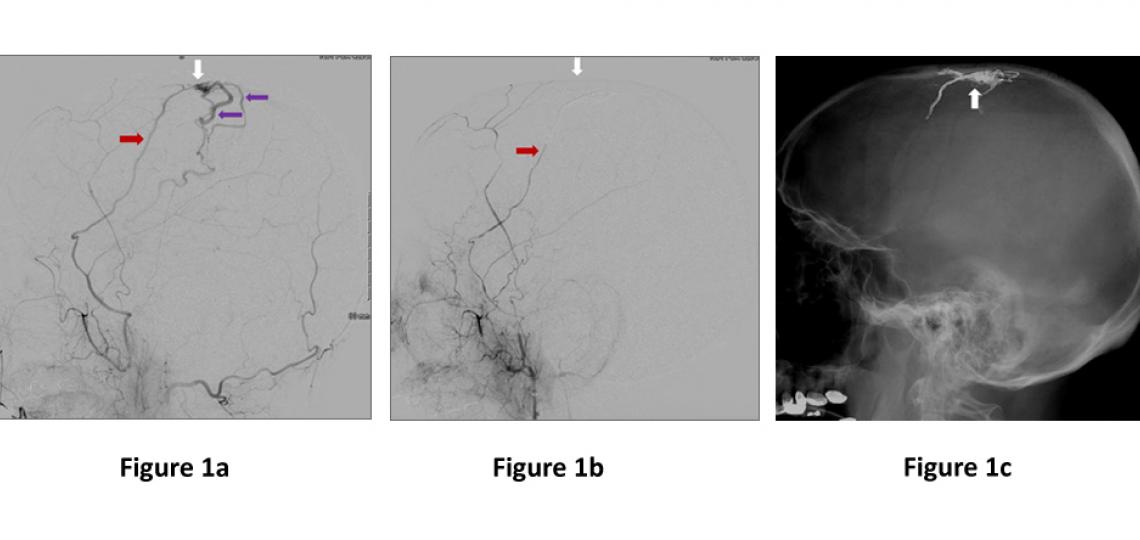

- Endovascular Embolization - This procedure entails passing a small catheter from a blood vessel in the groin up into the AVF, where glue or other material is injected into the abnormal vessel (Figure 1). This is the most common treatment of DAVF and is often curative.

Figure 1a: Lateral (side) view of a dural artery (red arrow) abnormally connecting to a large vein on the surface on the brain (white arrow), and high pressure arterial flow is immediately filling brain veins (purple arrows). Figure 1b. Immediately after embolization where glue was injected through the artery (red arrow) into the abnormal connection (white arrow) showing no more abnormal filling of the veins. Figure 1c. Lateral (side) view skull x-ray showing the glue material filling the area abnormal connection of the fistula (white arrow).